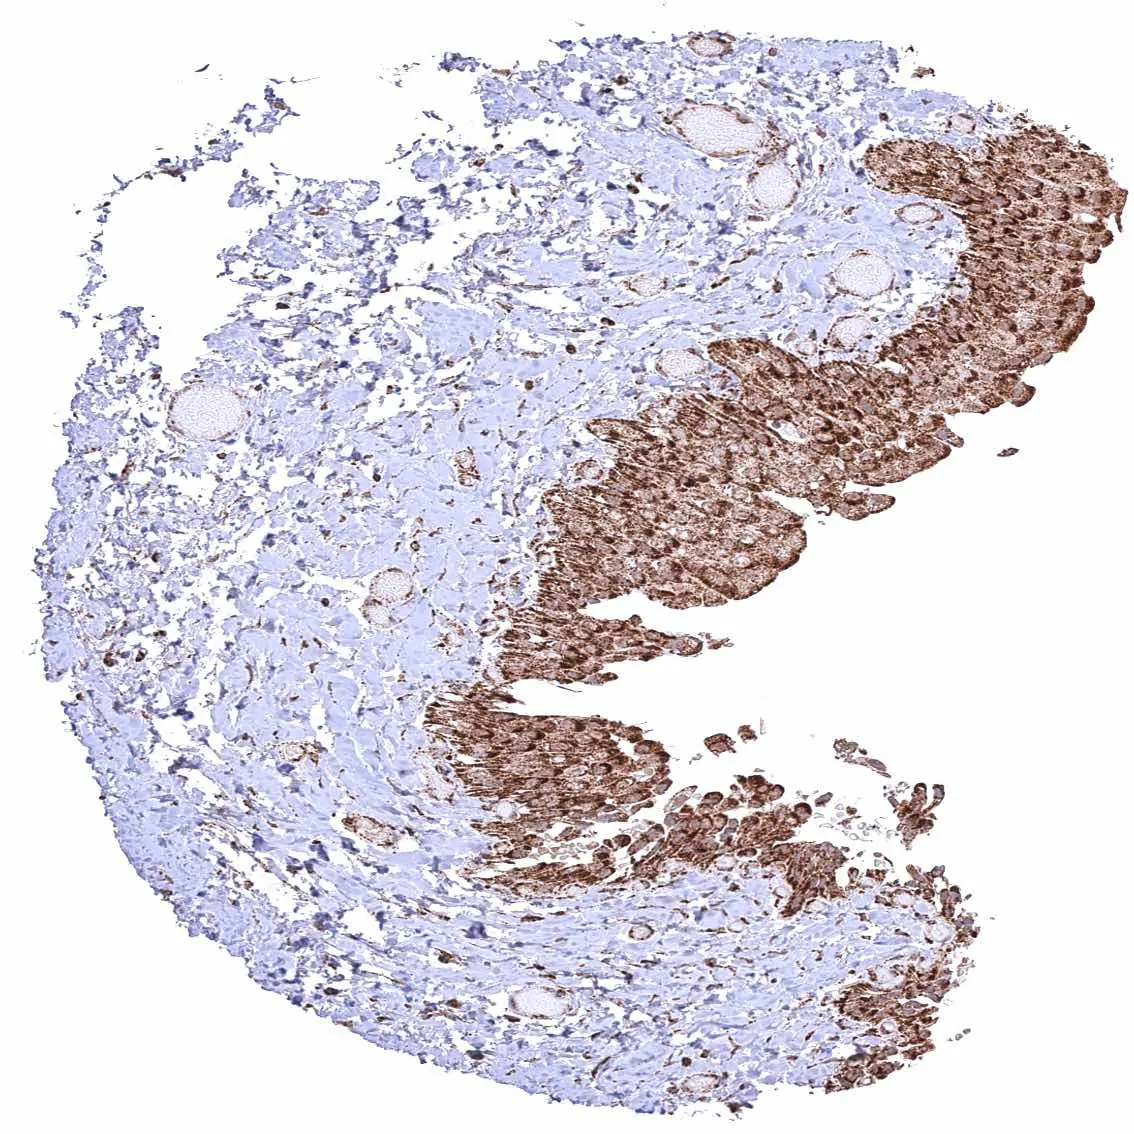

Adrenal gland – Cytoplasmic ATP5J staining occurs in all cell types. It is particularly strong in adrenocortical cells